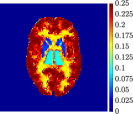

Figure 4, Figure 5, and Figure 6 show the mean images computed over the ten reconstructions obtained by the methods reg-AS-TR, reg-GN, and by the Matlab routine lsqcurvefit implementing a standard Trust-Region-Reflective least-squares algorithm [11, 10]. We used the noise-free IF and the perturbed IF with and of noise, respectively. Figure 7 contains mean and standard deviation values of the kinetic parameters computed over the ten reconstructions and over each one of the four homogeneous regions, for each one of the three noise levels on the IF.

In general, reg-AS-TR and lsqcurvefit seem to provide similar mean reconstructions, although uncertainties associated to lsqcurvefit are significantly bigger. On the other hand reg-GN seems to systematically underestimate the parameter values within region . Furthermore and as expected, for all methods the quality of the parametric reconstructions deteriorates with increasing noise levels; this is more clear from the and parametric images, probably due to the different sensitivities of the data with respect to the model parameters [37]. In reg-GN and lsqcurvefit some artifacts can be observed at the edges of the homogeneous regions, especially around region and region , whereas the effect of regularization in reg-AS-TR results in a reduced presence of artifacts while the structure of the regions is preserved. This general trend is confirmed by the error-bar plots of Figure 7. Finally, the frames in Figure 8 corresponding to reg-AS-TR show a significant improvement of the image quality with respect to what is provided by the other two approaches.